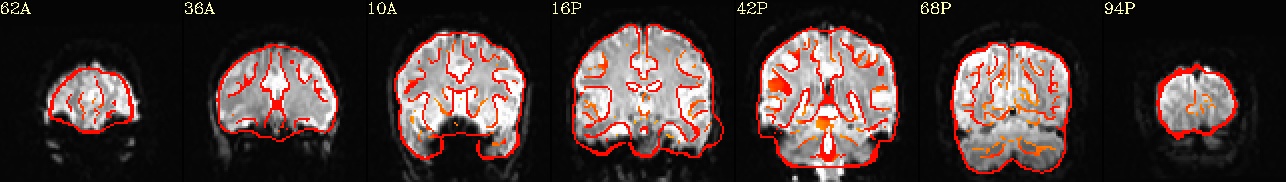

++ 3dmaskave: AFNI version=AFNI_21.2.00 (Jul  8 2021) [64-bit]

+++ 68948 voxels survive the mask

3dTcorr1D -prefix corr_brain errts.sub_08_REML+tlrc mean.errts.1D